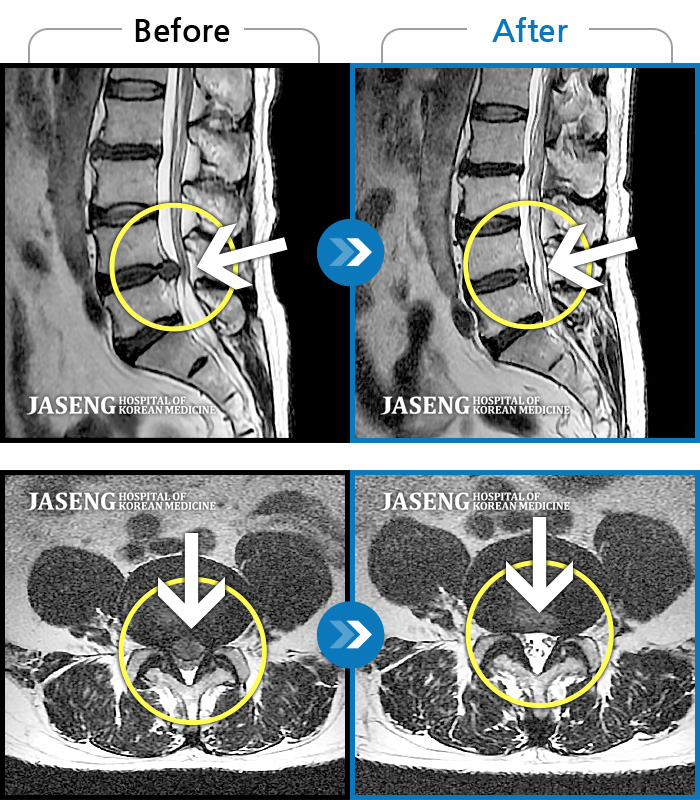

60건의 MRI 전후 사진으로 터진 디스크 흡수 사례를 확인하세요.

※ 환자분에게 사전 동의를 받아 동일 조건에서 촬영되었으며, 개인에 따라 치료 후 부작용이 발생할 수도 있으니 사전에 의료진과 상담 후 치료를 진행하시기 바랍니다.